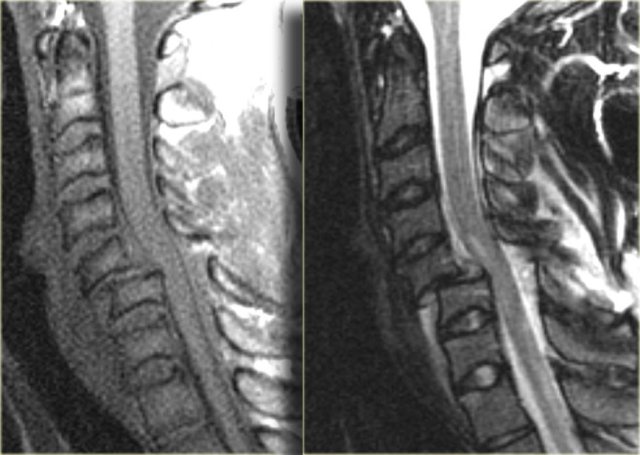

Hyperextension with superimposed spondylosis

On the left images of a 90-year-old male who tripped and fell on his back and the back of his head.

He had immediate quadriparesis after the event with no loss of consciousness.

First study the images on the left.

The findings are:

- Widening of the disc space C5C6 in the front and narrowing in the back.

- This is also called 'an open book'.

- It tells us that there was a hyperextension injury.

Continue with the CT-images.

On CT we also see that there has been a hyperextension injury.

The small black dots in the disc space are the result of a vacuum phenomena.

The negative pressure resulted in a vacuum phenomena in the injured disc space.

There is also some hyperdensity at the back of C5C6, which could be a herniated disc or just preexisting disc degeneration.

In such a patient with spondylosis which has led to narrowing of the canal, a low velocity injury can lead to spinal cord injury.

Continue with the MR-images.

The MR shows a subtle increase in signal intensity of the spinal cord.

Most of the time these patiets get a central cord injury.

There is only injury to the central part of the cord and these patients have disproportioned weakness of their arms and normal strength in their legs.

These injuries can be devastating, although it is uncommon that they are hemorrhagic.

Hyperextension injury (3)

On the left two other examples of this hyperextension injury.

It is easy to find the injured disc, since it is the one with the high signal (arrows).

Notice the prevertebral soft tissue swelling in the case on the right.